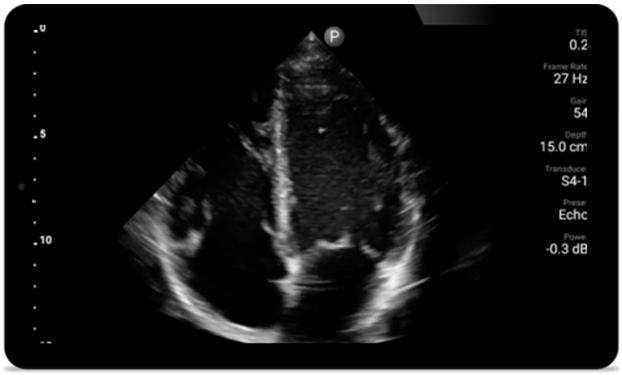

Third case image

Every second counts

in cardiac care

Heart attack patients need immediate care.

Lumify's cardiac presets can help patients get

diagnosed faster to improve their outcomes.